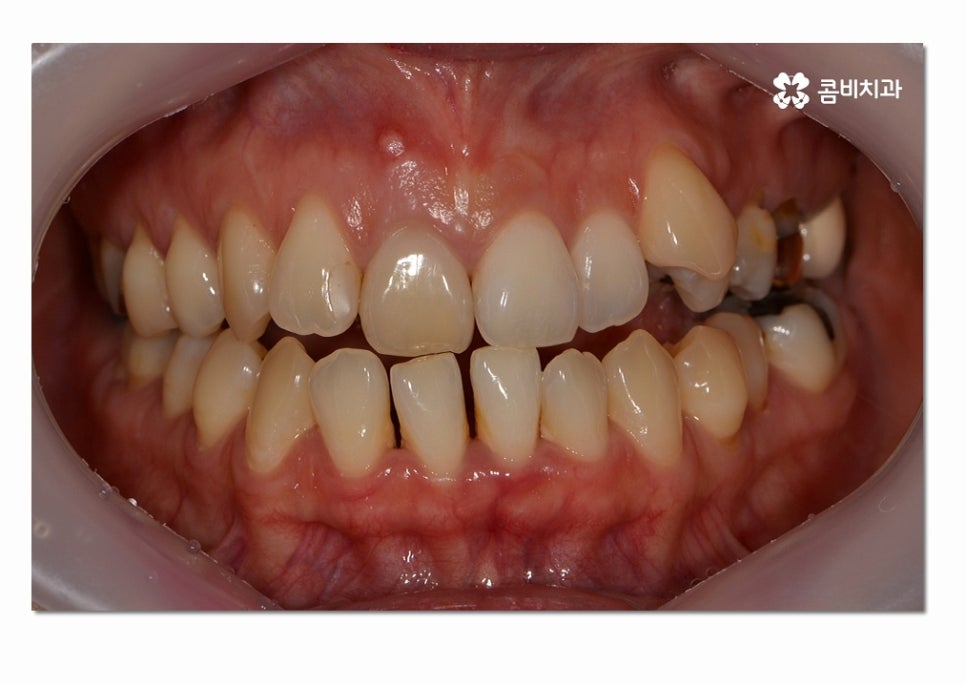

위 사례의 경우에는 3급 부정교합의 케이스로

치열이 맞지 않아 치아의 본래 기능들이 제대로 이루어지지 않고 있는 상태이며

서로 닿지 않아서 식사를 할 때마다 제대로 씹지 못하여

불편함을 느끼는 것은 물론이며 구강관리도 잘되지 않아서

충치가 많이 발생하고 있는 사례였다고 볼 수 있어요.